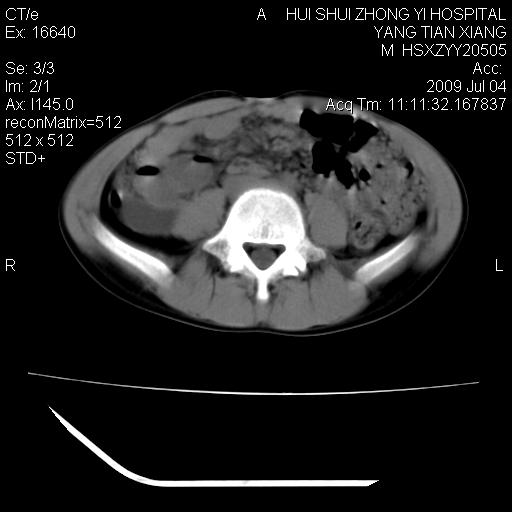

肝右叶胆管内见条状高密度影,脾脏增大,双肾上腺无异常;右肾正常结构消失,其实质内见类圆形低密度灶,ct值范围0-6hu,界清,右输尿管全程伴行多发低密度灶,界清,膀胱壁增厚,腹盆腔未见确切肿大淋巴结。

考虑:1、肝内多发胆管结石并肝内胆管扩张。2、右肾、输尿管多发脂肪瘤,多发平滑肌瘤?建议ct增强检查。4、膀胱壁增厚。

1)考虑右侧巨输尿管畸形。2)肝内胆管多发性结石。3)脾大。

右侧巨输尿管并神谕积水,左肾代偿性肥大,脾大,肝内胆管多发结石并胆管扩张。